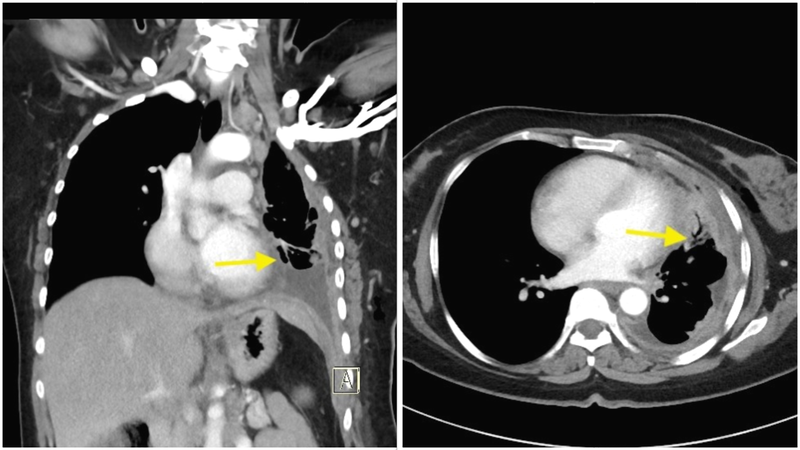

A. Contrast-enhanced computed tomography (CECT) of thorax (figure 2A &B)

Left: Figure 2A (coronal) & Right: B (axial): Diffuse pleural thickening, thickening of mediastinal pleura and pleural nodularity-Leung's criteria seen

Q. What are the CT findings suggestive of and what next?

A. Malignancy was considered as the diagnosis in view of positive Leung's criteria. We performed an ultra-sonographic guided diagnostic thoracentesis. The pleural fluid was dark yellow, exudative with lymphocyte predominance. The adenosine deaminase (ADA) levels were normal. The pleural fluid glucose was low (35 mg/dl). Pleural fluid analysis for cartridge-based nucleic acid amplification test (CBNAAT) was Mycobacterium tuberculosis (MTB) not detected. Pleural fluid cytology was negative for malignant cells.